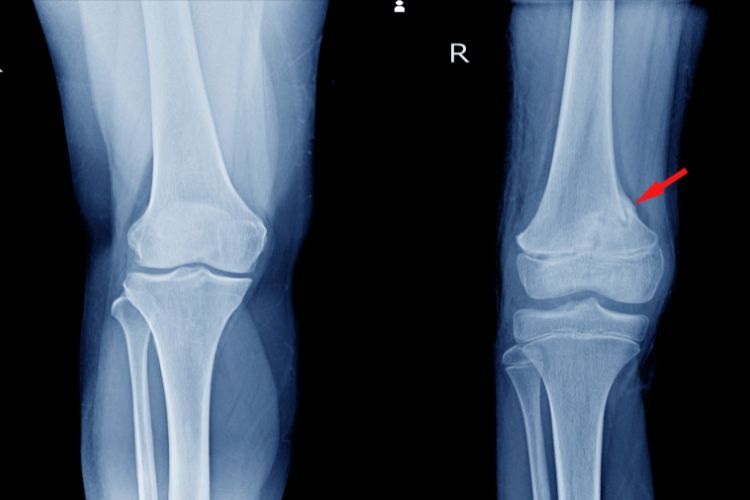

Rendgen (RTG) . Najčešći i osnovni test za potvrdu preloma. Omogućava uvid u položaj, tip preloma (poprečni, vertikalni, kominutivni) i eventualno pomeranje fragmenata. Radi se u različitim projekcijama (prednja, bočna, aksijalna) .